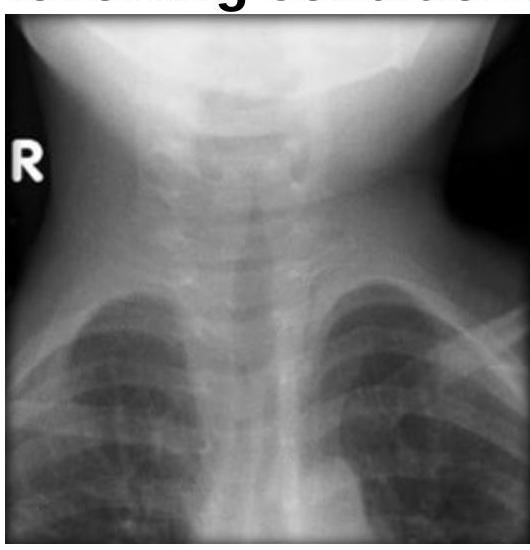

Steeple sign is seen in which of the following conditions?

Explanation: ***Acute laryngotracheobronchitis*** - The **steeple sign** on an anteroposterior (AP) neck radiograph is a classic finding in acute laryngotracheobronchitis, also known as **croup**. - This sign refers to the **subglottic narrowing** of the trachea, resembling a church steeple, due to edema caused by viral infection. *Acute epiglottitis* - Acute epiglottitis is characterized by the **thumb sign** on a lateral neck radiograph, where the swollen epiglottis appears enlarged. - This condition involves inflammation primarily of the epiglottis, not the subglottic region. *Laryngeal papillomatosis* - Laryngeal papillomatosis is characterized by **wart-like growths** (papillomas) on the vocal cords and larynx, often leading to hoarseness. - Radiographically, it typically appears as irregular soft tissue masses, not the diffuse subglottic narrowing seen in croup. *Bilateral abductor paralysis* - Bilateral abductor paralysis involves the inability of both vocal cords to abduct, leading to a **fixed, narrowed glottic opening**. - This condition presents as a smooth, constant narrowing at the level of the vocal cords rather than the subglottic, conical narrowing of the steeple sign.

Explanation: ***High pitched expiratory stridor*** - The image depicts an **omega-shaped epiglottis** and collapsed aryepiglottic folds, consistent with **laryngomalacia**. - Laryngomalacia typically presents with **inspiratory stridor**, not expiratory, resulting from airway collapse during inspiration. - **This is the EXCEPT answer** - high-pitched expiratory stridor is NOT a feature of laryngomalacia. *Omega shaped epiglottis* - The image clearly shows an **omega-shaped epiglottis**, a characteristic feature of **laryngomalacia**. - This anatomical variation contributes to the collapse of supraglottic structures during inspiration. *Cry is normal* - In laryngomalacia, the **vocal cords** themselves are not affected, so the **cry typically remains normal**. - The abnormal sounds (stridor) arise from the supraglottic structures, not the vocal cord function during crying. *10% cases need surgery due to development of OSA or Cor Pulmonale* - While most cases of laryngomalacia are self-limiting, approximately **10% of infants may require surgical intervention** (supraglottoplasty). - This is usually due to severe symptoms like **obstructive sleep apnea (OSA)**, failure to thrive, or the rare development of **cor pulmonale**.